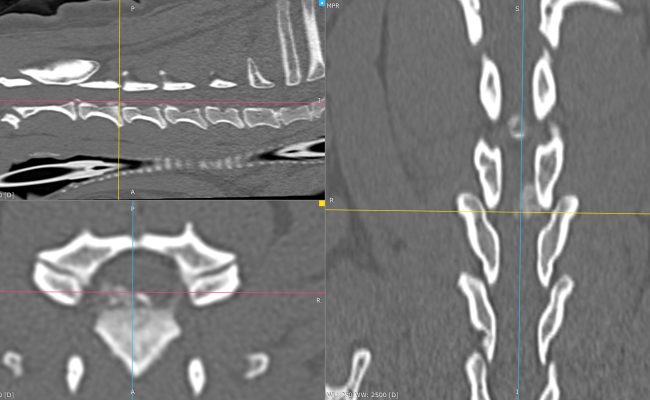

Scanner cervical pré- et postopératoire – Hernie discale C3–C4 traitée par corpectomie.

À gauche : examen tomodensitométrique préopératoire montrant une hernie discale cervicale C3–C4 nettement latéralisée à droite, responsable d’une compression médullaire.

Au centre : scanner de contrôle postopératoire immédiat avec reconstruction 3D, mettant en évidence une corpectomie C3–C4 parfaitement centrée sur l’espace intervertébral, conforme à la planification chirurgicale.

À droite : reconstruction multiplanaire postopératoire confirmant que la fenêtre de corpectomie permet une décompression complète de la moelle épinière, y compris sur la composante latéralisée de la hernie.